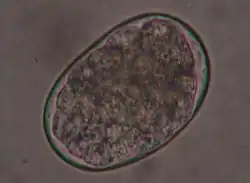

Females of A. caninum release eggs about 65×40 μm in size, which already have 4-10 furrowing stages at deposition. They are oval and thin-shelled and enter the outside world via feces. The prepatency is two to four weeks. The larvae released from the eggs can bore through the skin into a new host (percutaneous infection) or be ingested perorally - mostly via collective hosts such as rodents. As with T. canis, infection of puppies is also possible through the mother's milk (galactogenic infection). Larvae dormant in the mammary gland can be shed over a period of up to three suckling periods after a bitch has been infected once.[19]

The eggs of U. stenocephala are similar to those of A. caninum, but have a larger longitudinal axis of 85×45 μm. Infection occurs exclusively by peroral ingestion of larvae via contaminated food or collective hosts.